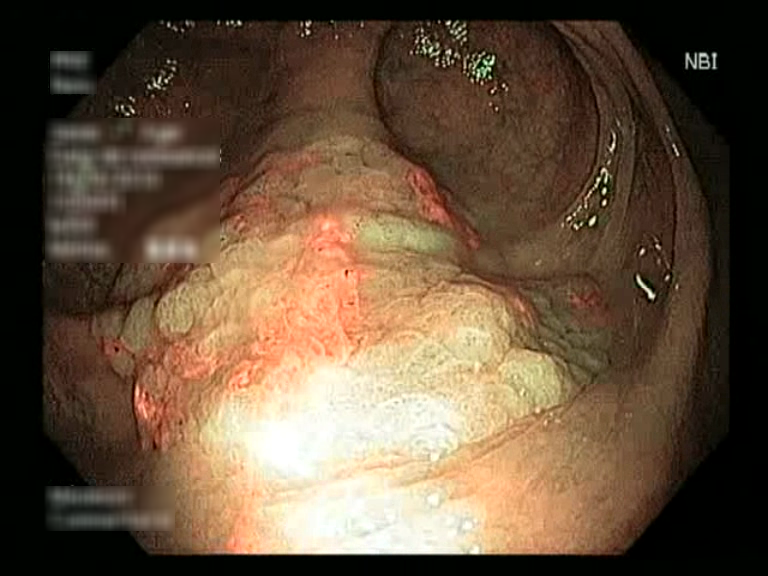

| Lesion | White Light Frame | NBI Frame | White Light Video | NBI Video | Camera Calibration |

| serrated_01 |  |

|

WL.mp4 | NBI.mp4 | cam.xml |